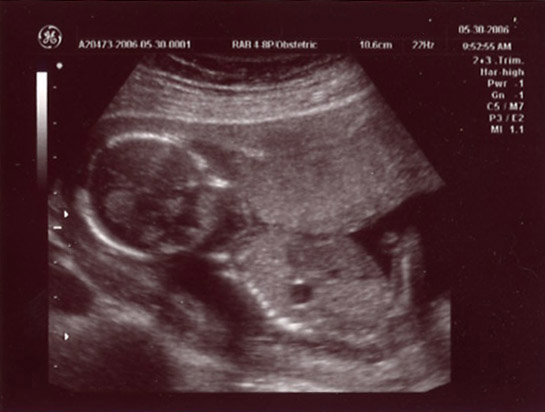

| May 30, 2006 - Sixteen Week Ultrasound! |

| Jen was feeling some pain this morning (May 30th), so to play it safe, she called her doctor. They said to come right in. We were obviously concerned, but they saw us right away and asked her a bunch of questions. They didn't think it was anything to be concerned with, but they

performed an ultrasound just in case. That too checked out and we left a bit relieved and happy to have even

more pics of our yet to be born angel. ~Chris |